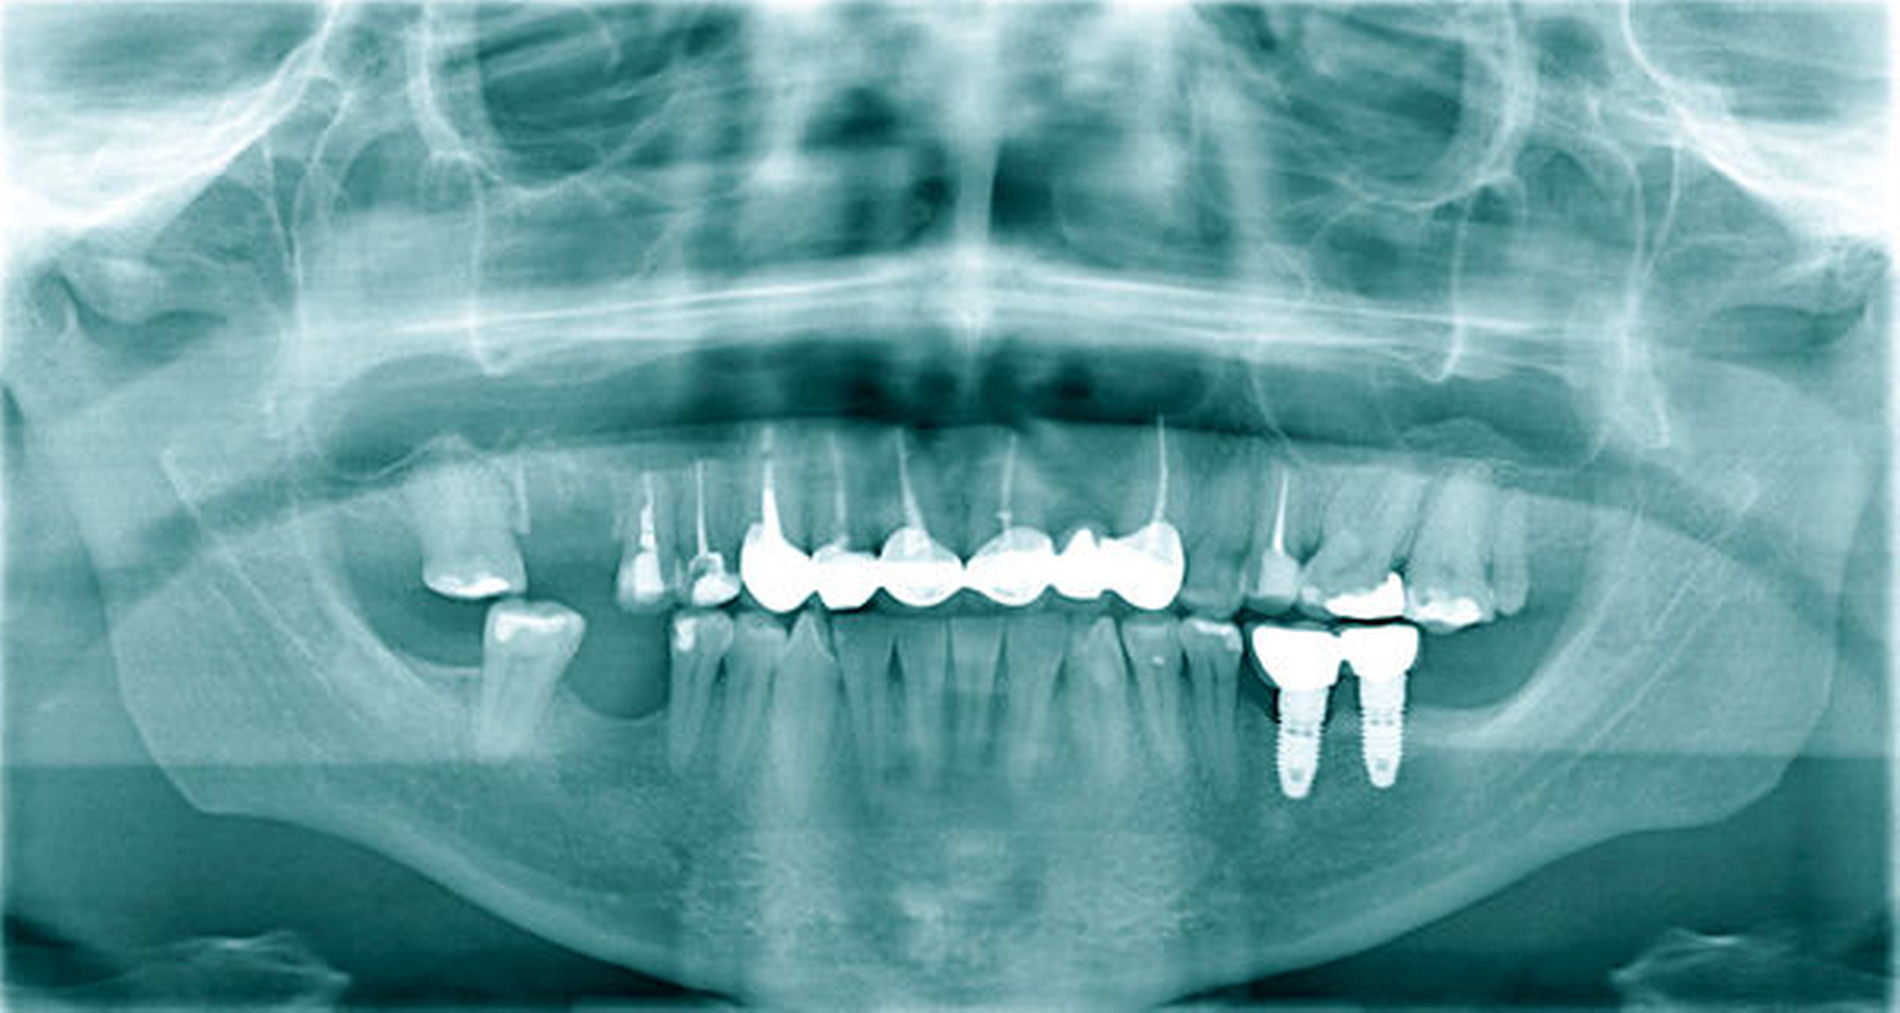

In Intubationsnarkose folgte die Zystektomie (Abbildung 3) über einen marginalen Randschnitt vestibulär regio 17 bis 24.

Dabei wurde die rechte Kieferhöhle über den distalen Zystenanteil im Sinne einer Zystantrostomie eröffnet. Die Zähne 13 und 15 wurden wurzelspitzenreseziert und retrograd wurzelgefüllt sowie die Zähne 14, 12, 11, 21 und 23 orthograd wurzelgefüllt und im Anschluss wurzelspitzenreseziert (Abbildung 4). Intraoperativ wies der Zahn 16 im Bereich der distobukkalen Wurzelspitze eine Paro-Endo-Läsion auf, so dass wir uns entschieden, diesen zu entfernen. Abschließend erfolgten ein Gingivaverschluss sowie die Deckung der iatrogen entstandenen Mund-Antrum-Verbindung in regio 016 mit einem Rehrmann-Lappen.

Die postoperative Wundheilung verlief stadiengerecht, so dass wir die Patientin mit den obligaten Verhaltensmaßnahmen nach Verschluss einer Mund-Antrum-Verbindung am fünften postoperativen Tag in die ambulante Nachsorge entlassen konnten. Das postoperative Orthopantomogramm dokumentiert den Bereich der resezierten Zyste mit seiner Zystantrostomie zur rechten Kieferhöhle, den vollständig entfernten Zahn 16 sowie die durchgeführten endodontischen Maßnahmen (Abbildung 4). Die abschließende Histologie ergab eine radikuläre Zyste ohne Anhalt auf Malignität.